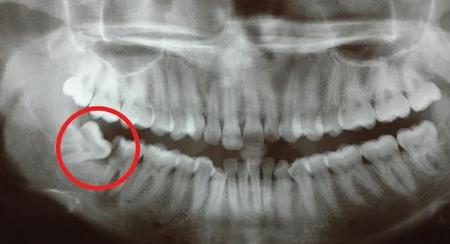

为什么会长智齿?是不是一定要拔掉?

智齿为第三颗磨牙,大部分情况下智齿被认为是进化的残余,正在逐渐消失。但是智齿到底是完全由基因遗传决定还是后天影响的仍然有待进一步确定,许多学者现在提出,童年时期的饮食和...